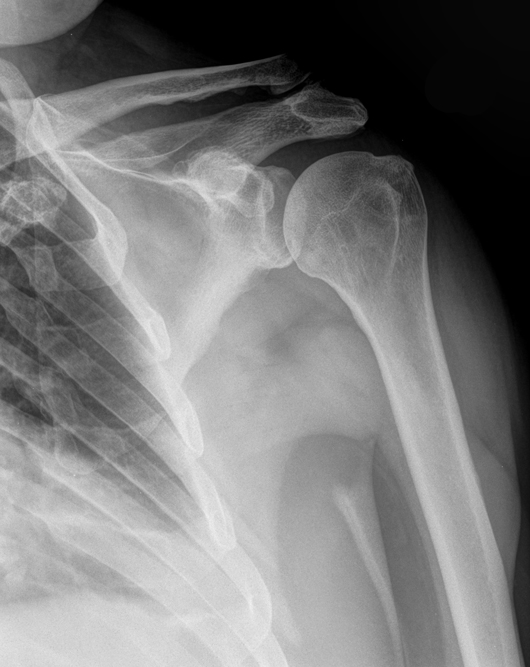

Sturz von der Treppe

So sieht es aus wenn man von der Treppe stürzt und auf eine 37 Jahre alte Verletzung fällt.

röntgenbild-Dezember-2017